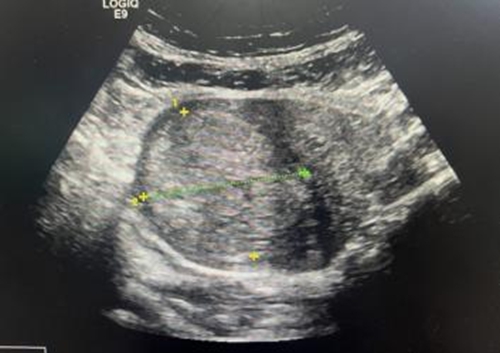

手術過程十分順利,術中患者無不良反應,術前血運豐富的病灶,術后造影顯示血供已完全消失,消融效果非常滿意。張女士恢復良好,術后3天就順利出院了。

#術后盆腔增強磁共振 >>

術后半個月,胎盤組織就自行排除,超聲提示植入的胎盤病灶明顯縮小。術后1個月再次復查超聲,胎盤已自行排除干凈,宮腔內沒有異常回聲。